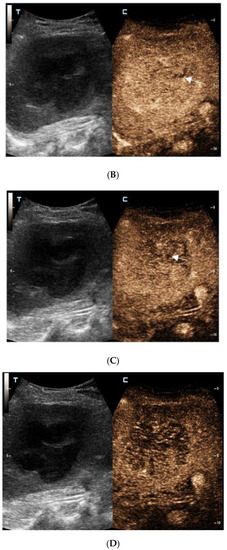

Ultrasound-Guided Coarse Needle Biopsy Diagnosed Isolated Hepatic Malignant Melanoma with Undetermined Origin in TB Patient: A Case Report

Chen, K.; Dong, Y.; Zhang, W.; Han, H.; Mao, F.; Zhang, H.; Wang, W. Ultrasound-Guided Coarse Needle Biopsy Diagnosed Isolated Hepatic Malignant Melanoma with Undetermined Origin in TB Patient: A Case Report. Diagnostics 2023, 13, 42. https://doi.org/10.3390/diagnostics13010042